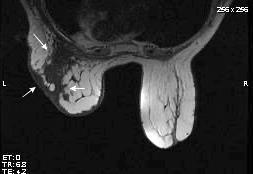

Tumor desmoide (“Fibromatosis agresiva”)

T1: Isointensos con músculos.

T2: Señal intermedia y de alta intensidad.

Presencia frecuente de áreas curvilíneas y lineales dentro de la lesión

Mansour J et al. Diagnostic and Imaging Approaches to Chest Wall Lesions. Radiographics 2022